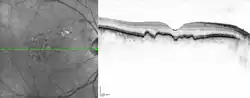

Drusen in optical coherence tomography.

Drusen associated with aging and macular degeneration are distinct from another clinical entity, optic disc drusen, which is present on the optic nerve head.[2] Both age-related drusen and optic disc drusen can be observed by ophthalmoscopy. Optical coherence tomography scans of the orbits or head, calcification at the head of the optic nerve without change in size of globe strongly suggests drusen in a middle-age or elderly patient.